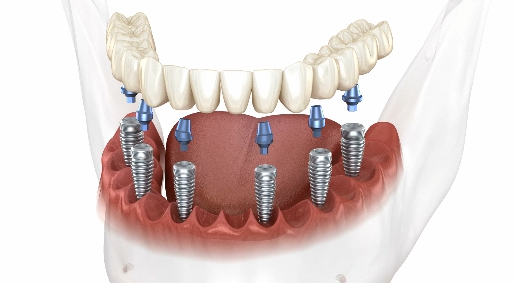

治療方案一

傳統全口植牙

傳統全口植牙雖然初期費用較高,

但能長期使用,並提供最接近真牙的自然咀嚼功能。

因此,「最大化植牙」或「全弓植牙」通常被視為最佳選擇。

不過,一般成年人上顎有 14 顆牙,下顎也有 14 顆牙,

合計共 28 顆牙齒。

若是每一顆缺牙都進行植牙,治療費用將變得過於沉重。

這就是為什麼我們會根據患者的口腔狀況及多種個別因素,

來尋找合理、可行的治療方案。